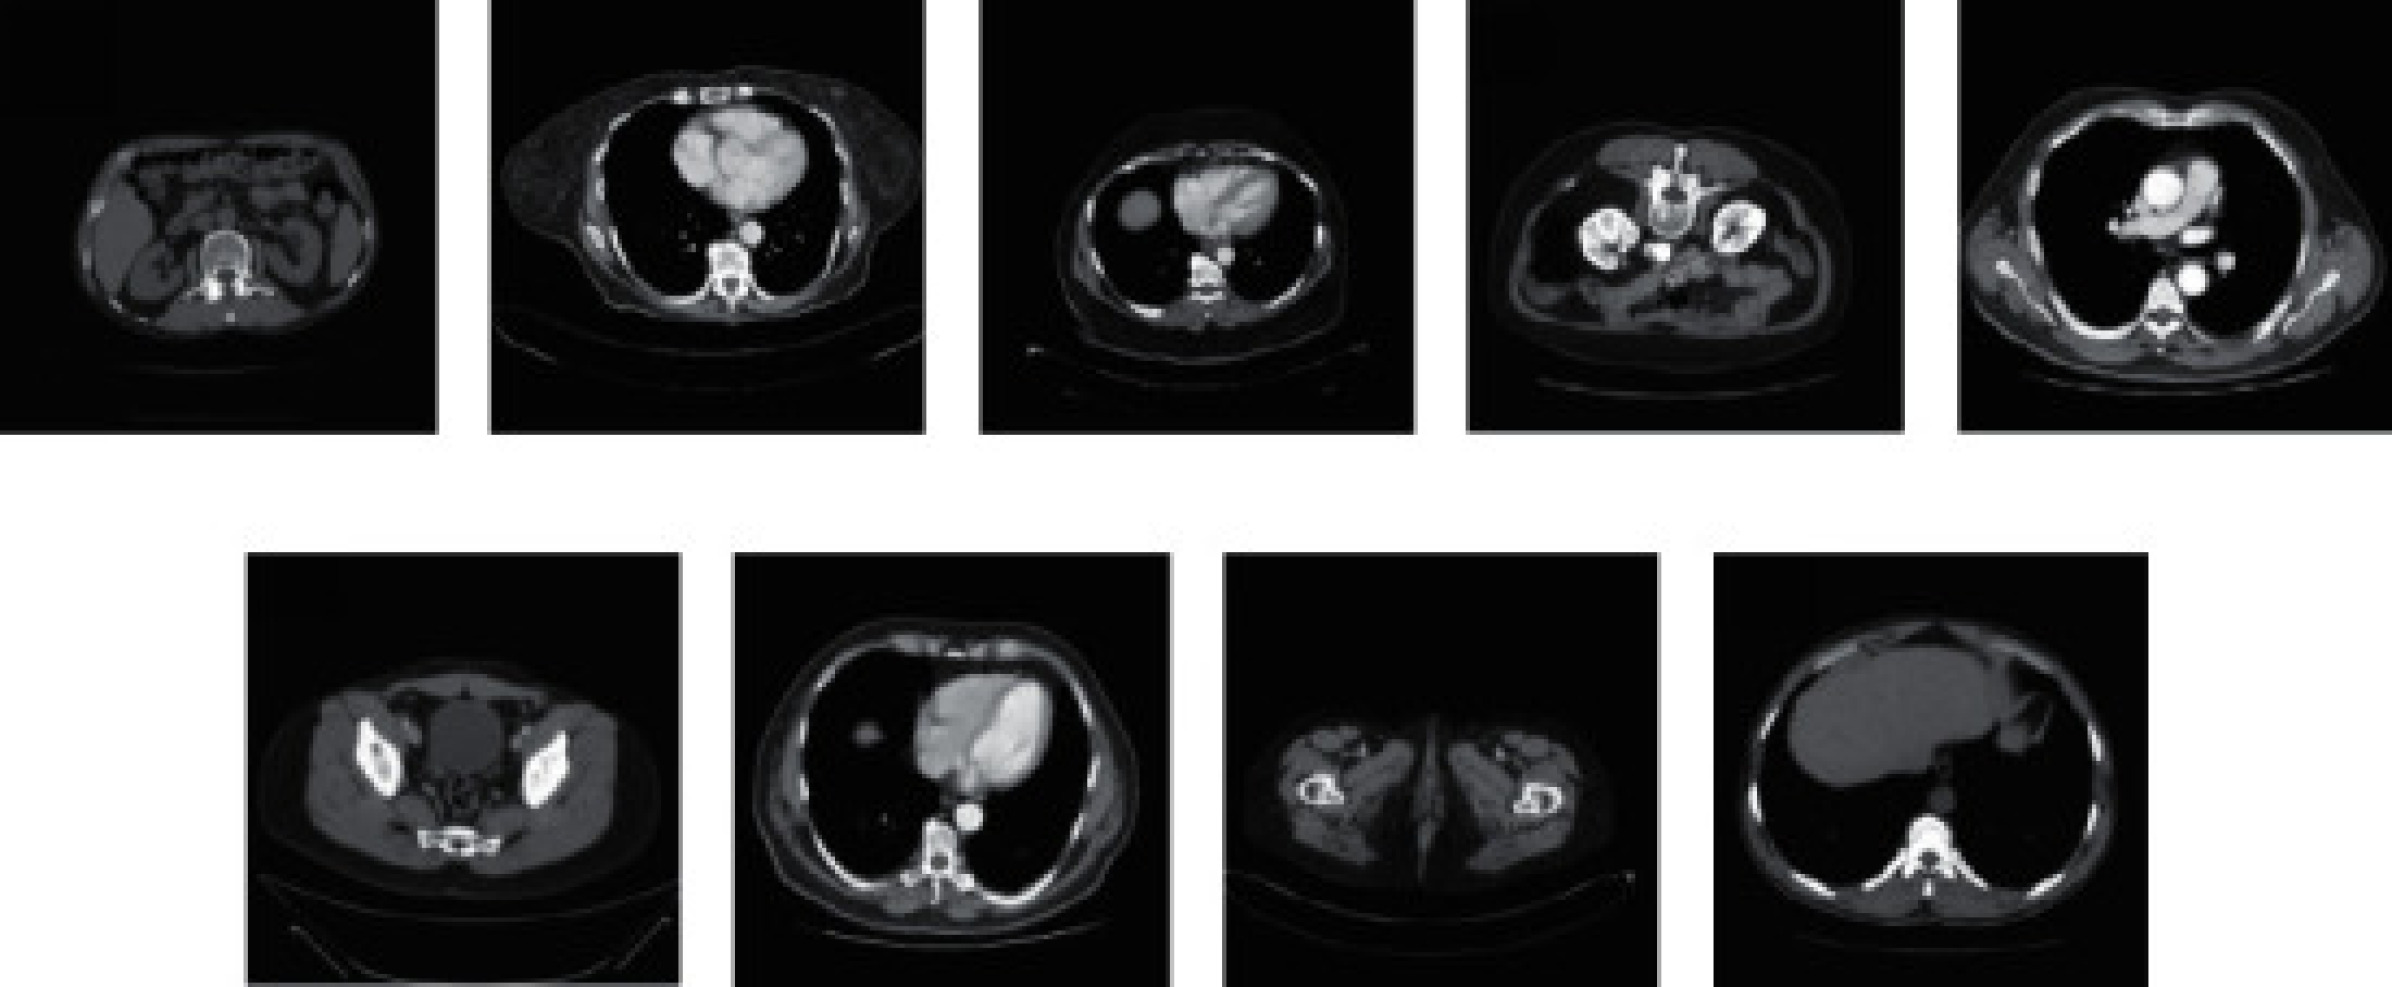

From the TCGA-COAD clinical dataset, nine CT images were chosen at random to serve as evaluation samples. These were distinct and did not coincide with the 200 images earmarked for training purposes, as illustrated in Figure 2. For comparative analysis, this study utilizes the WGAN algorithm and the foundational RED-CNN algorithm . The noise reduction capabilities of these methods are exemplified in Figure 6, where sample (a) and sample (c) from Figure 5 are used to demonstrate the denoising outcomes.

Refer to caption

Figure 2: A case study for CT image denoising.